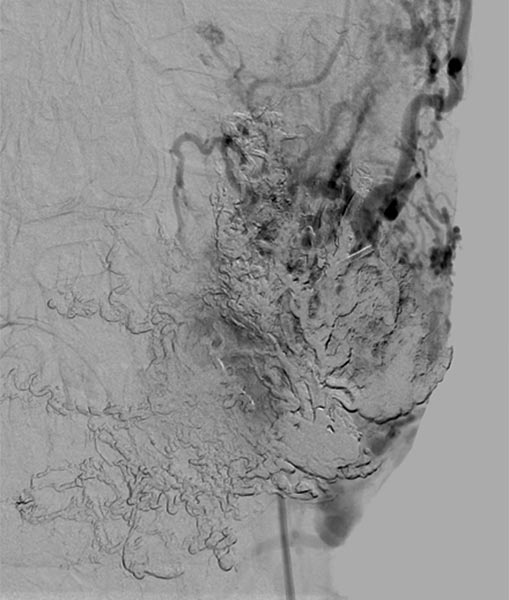

Lateral view of a digital subtraction angiography after contrast injection into the left external carotid artery. The AVM is visible as a diffuse, reticular net-like nidus with direct, strong venous outflow centrally in the left cheek (fast-flow malformation).

Lateral view, DSA after contrast injection in the left internal carotid artery. There is also a massive supply to the nidus of the AVM from the internal carotid artery, mainly via the ophthalmic artery and the meningohypophyseal trunk.

This complicates embolization therapy considerably.

DSA, anterior-posterior view, after injection into the right common carotid artery. The nidus of the AVM on the left cheek is also supplied from the contralateral right external carotid artery and right facial artery.